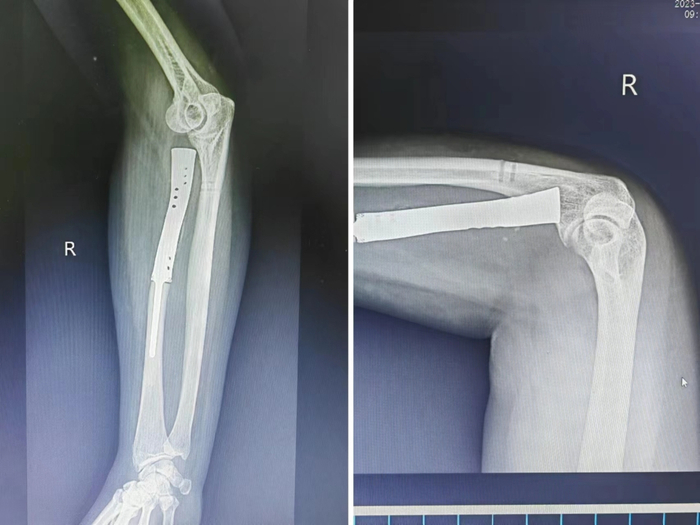

手术情况

术后情况